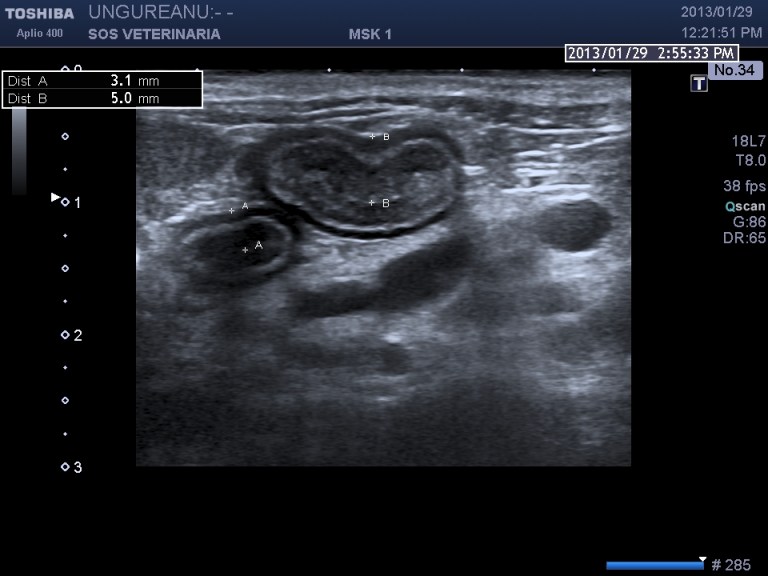

Caso 2

PROCESSO INFILTRATIVO DUODENALE E DELLA PAPILLA  (infiammatorio o neoplastico)

gatto comune europeo 9 aa ABC_8738

Le vie biliari del gatto hanno caratteristiche diverse rispetto al cane il dotto pancreatico principale raggiunge il coledoco  prima che questo defluisca nella papilla duodenale maggiore (nel cane lo sbocco e’ indipendente) ,inoltre il dotto accessorio  sfocia nella papilla minore ,un processo ostruttivo distale porta quindi a distensione  di entrambe le componenti  ,l’iperplasia della parete delle vie biliari  puo’ essere indicativa di flogosi o di cronicita’ dell’ostruzione  (in questo caso la parete e’ normale) ma come sopraesposto la diagnosi richiede spesso invasivita’ ,questo caso purtroppo  non ha seguito nessuna diagnosi ,il soggetto non ha risposto alla terapia cortisonica (l’unica che ha voluto tentare il proprietario) e antibiotica e si e’ perso nel foll’up, Una laparotomia esplorativa con campionamento del tessuto iperplastico  e coltura biliare era a mio avviso unica opzione possibile per una corretta diagnosi .

Il caso si mostra interessante sul piano dell’imaging che evidenzia la complessita’ delle vie biliari extraepatiche e pancreatiche dilatate.